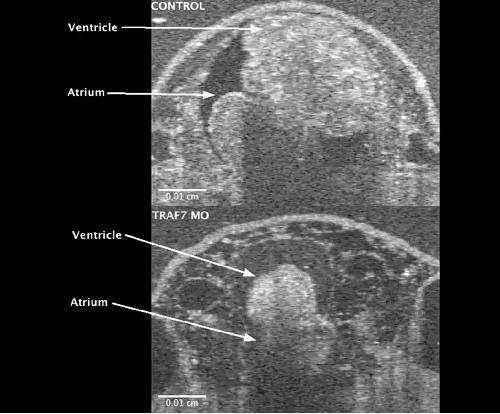

Pleiotropic role of TRAF7 in skull-base meningiomas and congenital heart disease., Proc Natl Acad Sci U S A 2023 |